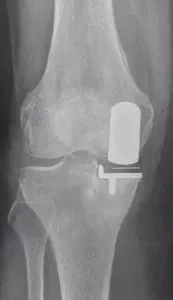

Partial knee replacement (also called unicompartmental knee replacement) is a bone-conserving surgical procedure which is an alternative to total knee replacement where only the damaged part of the knee joint is replaced with an implant, rather than the entire knee

- Only one part of the knee is replaced